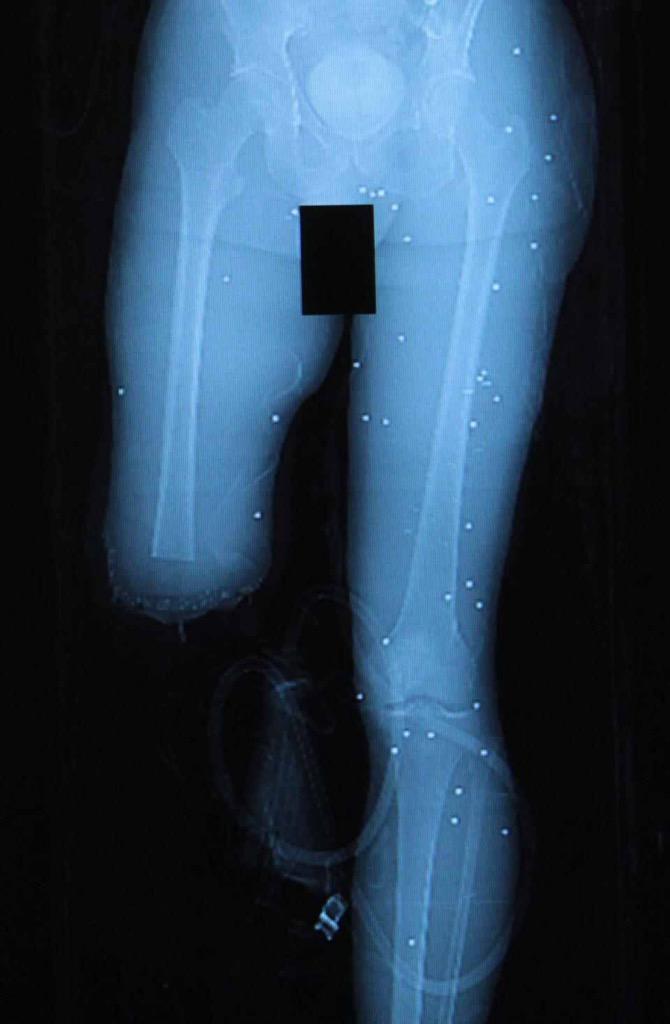

These came into evidence today; it's the BBs and shrapnel still embedded in Marc Fucarile's body. #Tsarnaev

CDTLzOcUMAEaISg.jpg

CDTLzOcUsAA2IsM.jpg

CDTLzOkUsAAopYZ.jpg

Jim Armstrong @JimArmstrongWBZ · Apr 23